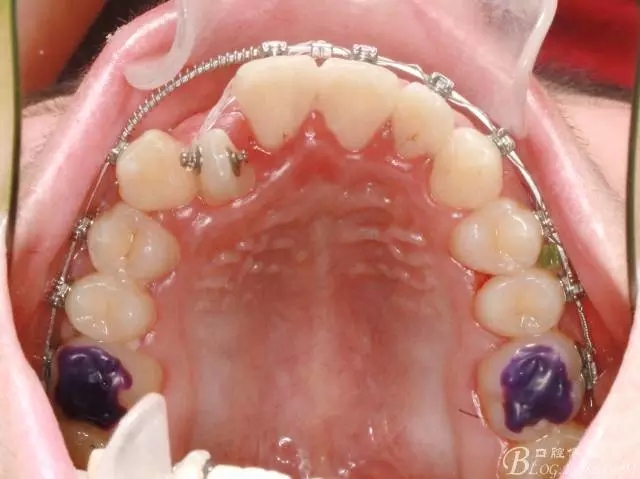

在活動(dòng)頜墊輔助下打開(kāi)咬合,并對(duì)上頜排齊、擴(kuò)弓;

此期間要避免前牙咬合干擾;

牽引側(cè)切牙時(shí)要保持中線的位置;